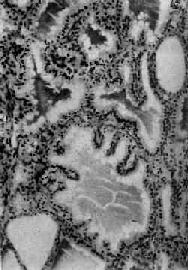

2.胶质贮积期长期缺碘使滤泡上皮反复增生、复旧,少数滤泡上皮仍呈现增生肥大,保持小型滤泡增生状态,但大部份滤泡显著扩大,内积多量浓厚的胶质,上皮细胞受压变扁平(图15-4)。肉眼见甲状腺弥漫肿大,可达200~300g(正常20~40g),表面光滑,无结节形成,质地较软,切面呈淡褐色,半透明胶冻状(图15-5)。此期可称为弥漫性胶样甲状腺肿(diffuse colloid goiter)。

图15-4 地方性甲状腺肿

甲状腺滤泡显著扩大,腔内充满均匀的胶质,上皮细胞变扁平